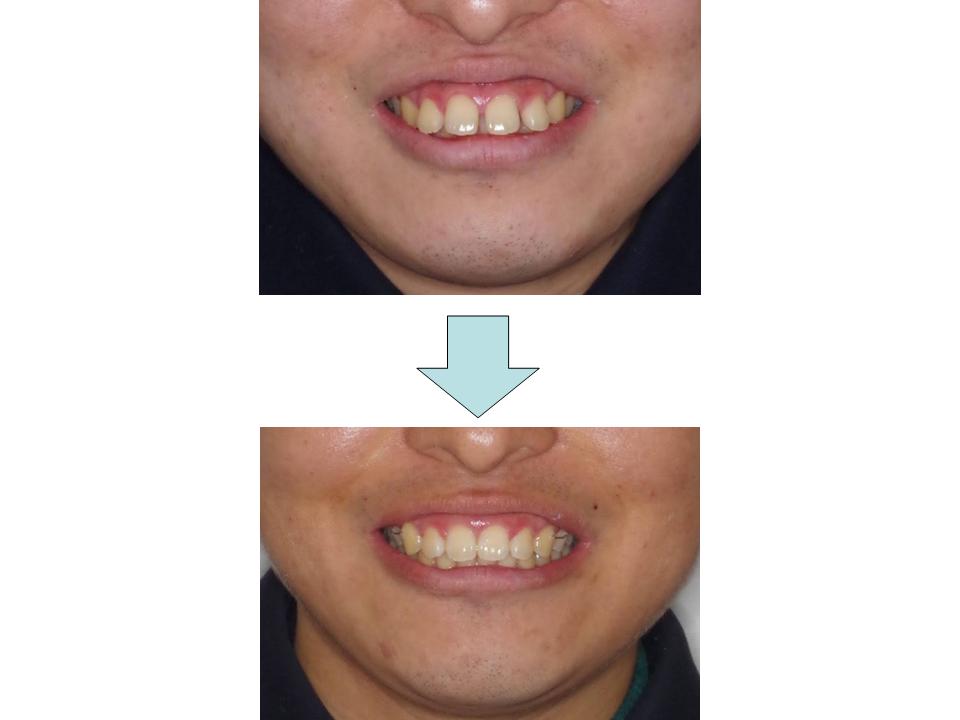

上の前歯が重なっている

上下の前歯の凸凹の原因が歯とあごの大きさのバランスの乱れと左側の上下のかみ合わせのずれであり、口元が正常であることから親知らず以外を抜かずにわずかに歯を削ることと左上の奥歯を後ろに下げることで歯ならびの改善を試みました。適切な装置の使用により、最終的に理想的なかみ合わせにすることができました。

| 主訴 | 上の前歯が重なっている |

| 年齢・性別 | 24歳 / 男性 |

| 抜歯部位 | 上下顎両側智歯 |

| 装置 | マウスピース型矯正装置(インビザライン) |

| 期間 | 1年2か月 |

治療前

治療中

治療後

費用(すべて税別)

治療費840,000円

通院回数14回